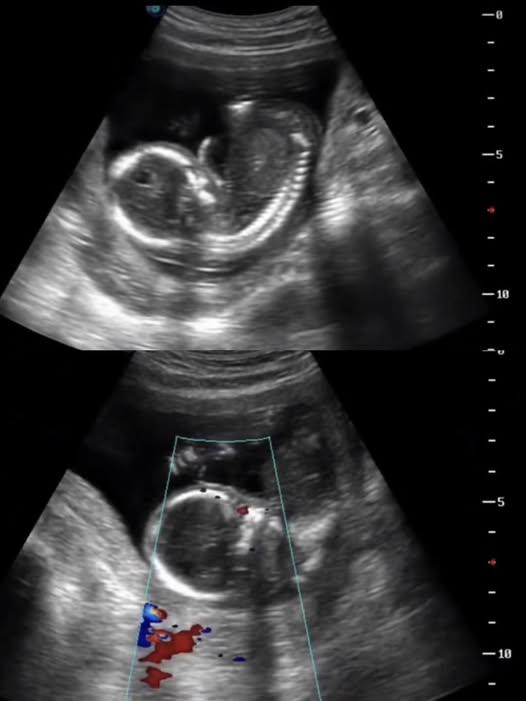

Thai phụ mất con sau khi bị buộc về quê làm cỗ: Câu chuyện khiến cộng đồng xót xa và cảnh báo nguy cơ cho mẹ bầu- Ảnh 2.

Bên cạnh đó, làm việc quá sức, đứng lâu, cúi gập người, bê vác nặng hoặc căng thẳng kéo dài có thể làm tăng co bóp tử cung, dẫn đến dọa sảy thai, sinh non hoặc thai lưu. Stress tâm lý cũng là yếu tố nguy hiểm, bởi nó có thể ảnh hưởng đến nội tiết và gián tiếp tác động xấu đến thai nhi.

Mỗi thai kỳ là một hành trình cần được theo dõi và bảo vệ nghiêm ngặt. Khi bác sĩ đã chỉ định nghỉ ngơi, gia đình tuyệt đối không nên ép thai phụ di chuyển hay lao động vì bất kỳ lý do nào, kể cả những lý do mang tính truyền thống hay trách nhiệm gia đình.